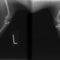

■ 症例20 ポメラニアン 8ヶ月 1.8kg

左右膝蓋骨脱臼 グレードⅢ

2ヶ月前から間欠的跛行が認められ、両膝の膝蓋骨脱臼整復術を行った。

手技は縫工筋及び内側広筋の解放、脛骨粗面の外側転位、滑車ブロック形造溝術、内外側関節包の縫縮を選択し実施した。

右側の膝蓋骨脱臼は上記手技で整復されたものの、左側はそれのみでは膝蓋骨が浮く様子が認められた。その為、PDS縫合糸にて膝蓋靱帯を1糸のみ縫合し、靱帯の縫縮を行った。

膝蓋骨脱臼は膝関節における膝蓋骨の内外側の脱臼と定義されるが、時として単純な内外の脱臼ではなく、膝蓋骨が大きく前方に浮き上がるように脱臼する場合がある。特にトイプードルやポメラニアンといった犬種に多く認められる。

内側脱臼に加えて前方への浮き上がりを矯正する為に、従来より脛骨粗面転移により膝蓋靭帯を外方と下方に引っ張り、固定する方法を選択する。膝蓋骨の前方への浮き上がりが軽度の場合は、従来法ではなく関節包の縫縮で対応していた。しかし、一部の症例で膝蓋骨の動きが悪くなり伸展機構が円滑に機能せずロボット様歩行になるケースがあった。

その為、膝蓋靭帯自体を縫縮する方法を採用した。この方法により、膝関節の伸展機構を妨げず膝蓋骨の軽度の浮きを矯正することが可能となった。

本症例の経過は良好である